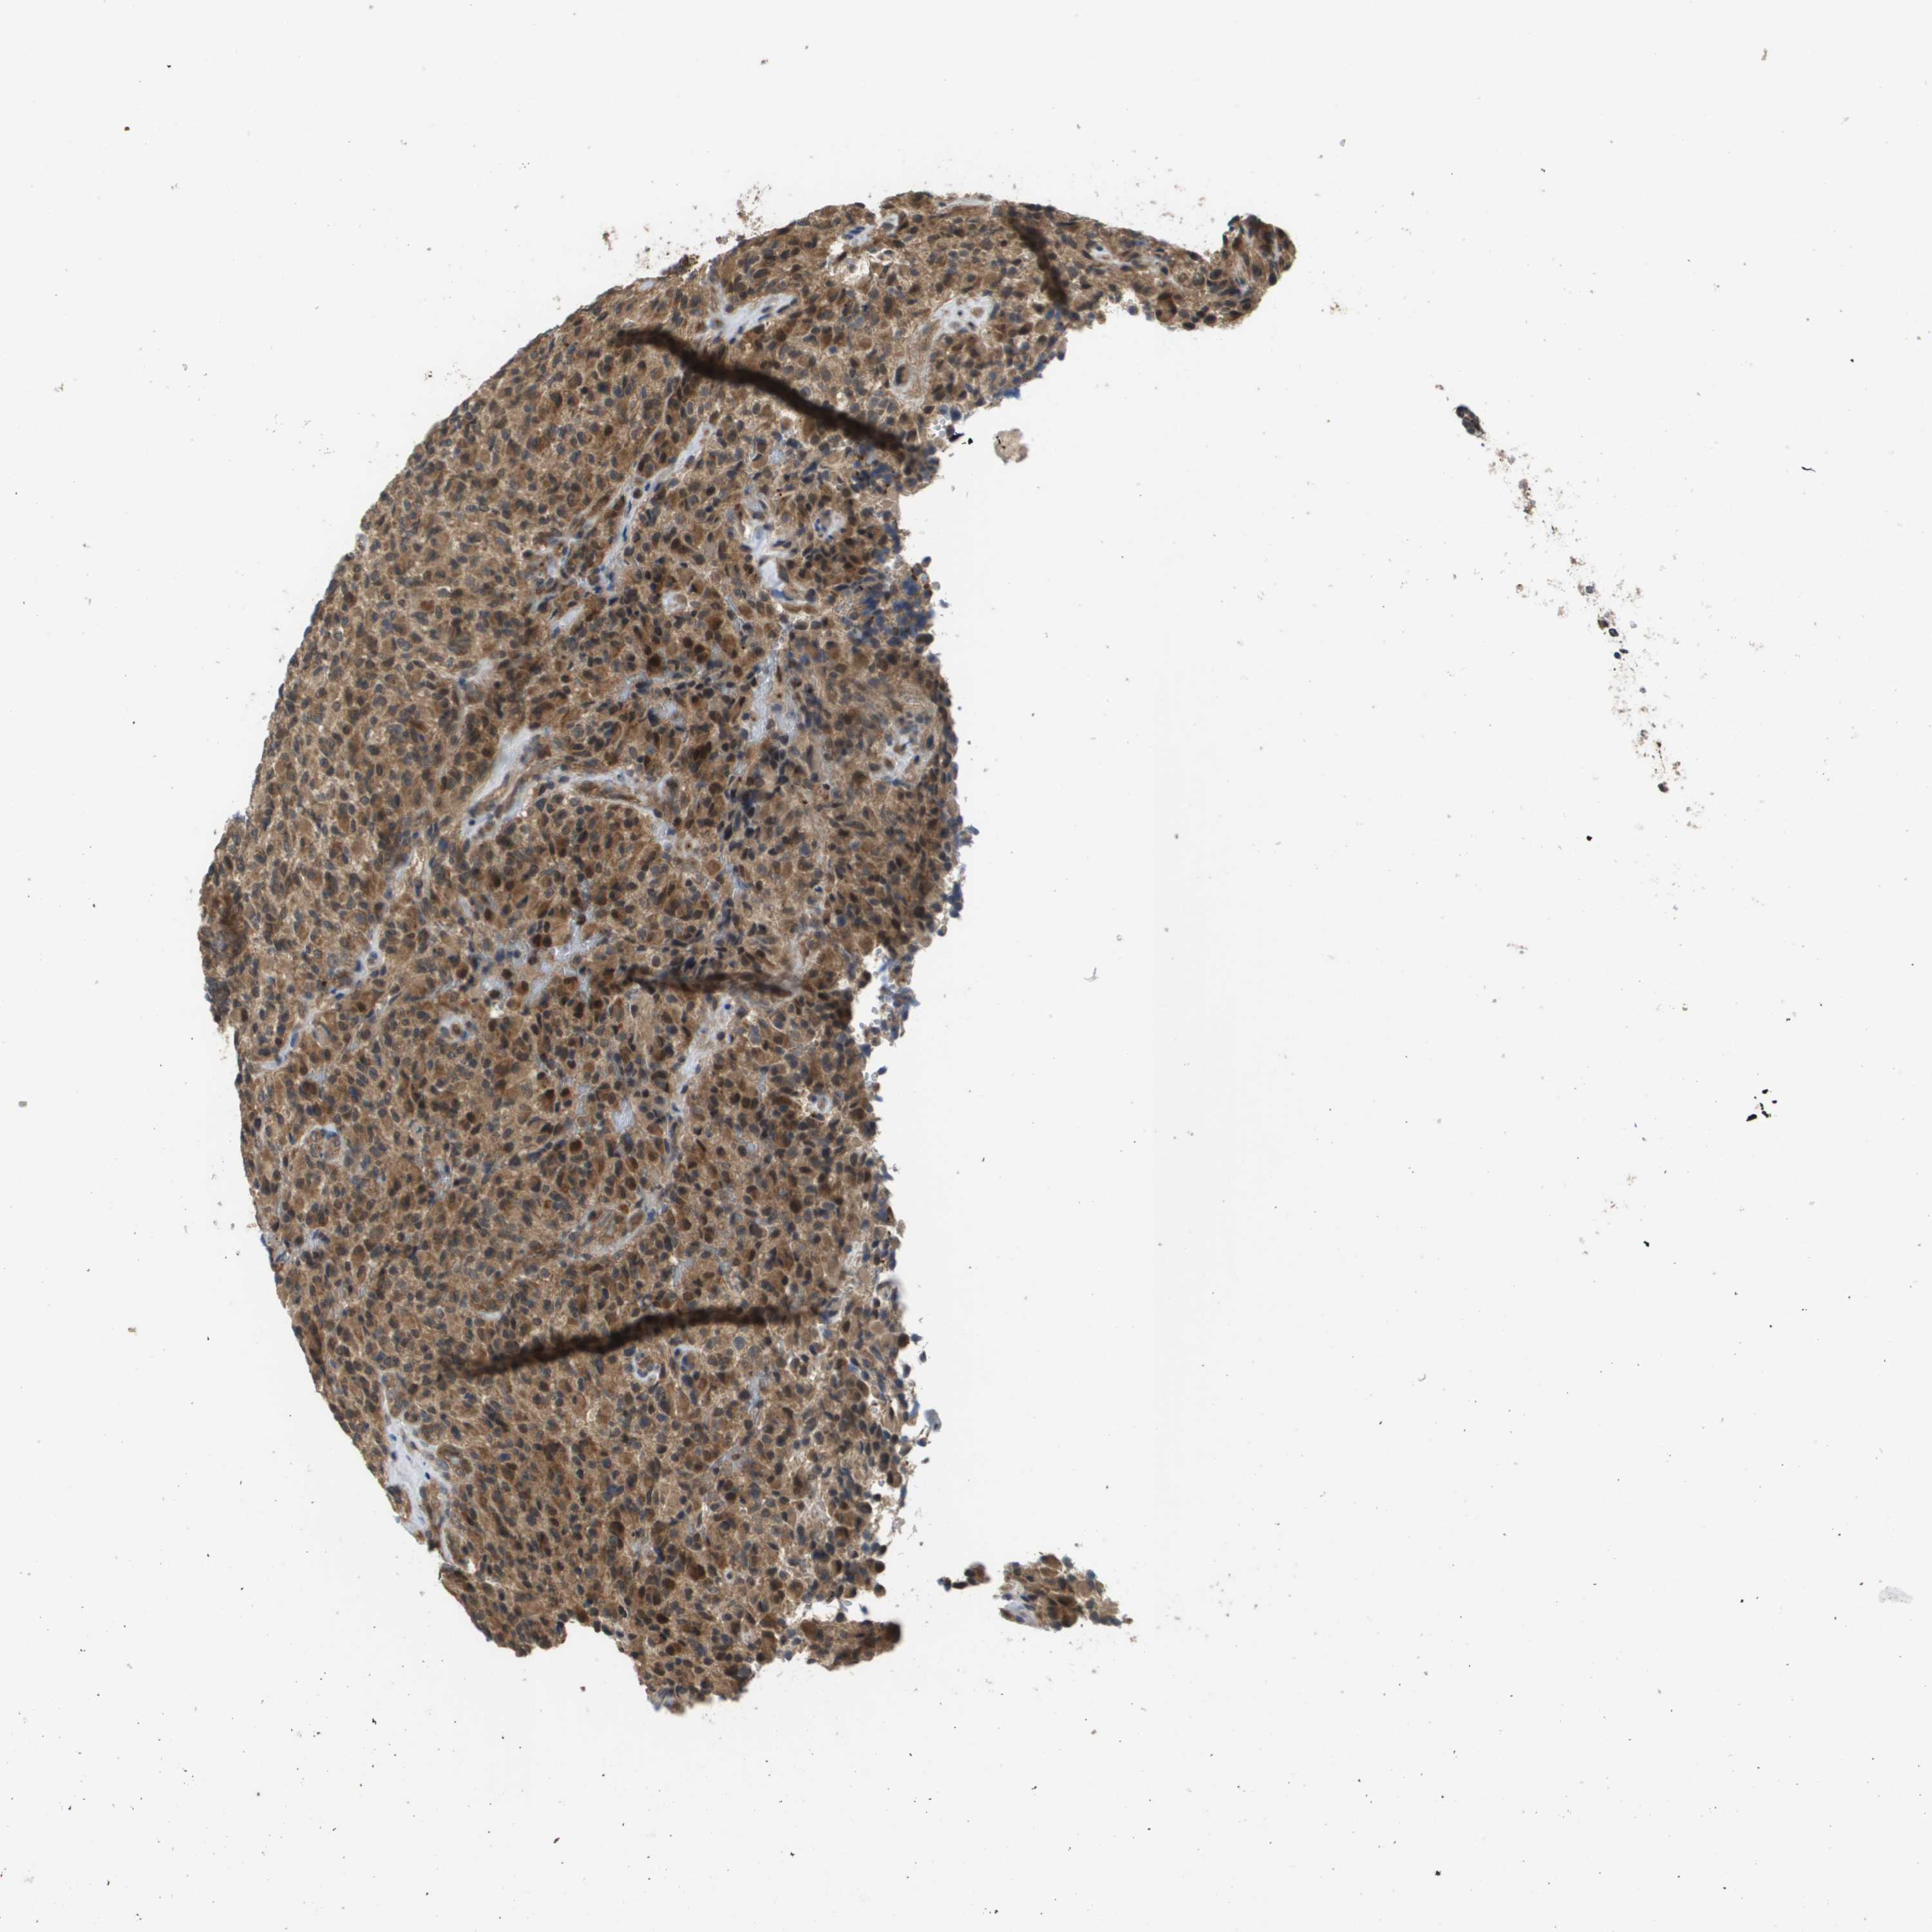

GLIOMA - Protein expressioni

A mouse-over function shows sample information and annotation data. Click on an image to view it in a full screen mode. Samples can be filtered based on level of antibody staining by selecting one or several of the following categories: high, medium, low and not detected. The assay and annotation is described here.

Note that samples used for immunohistochemistry by the Human Protein Atlas do not correspond to samples in the TCGA dataset.

Antibody stainingi

Antibody staining in the annotated cell types in the current human tissue is reported as not detected, low, medium, or high, based on conventional immunohistochemistry profiling in selected tissues. This score is based on the combination of the staining intensity and fraction of stained cells.

Each image is clickable and will lead to virtual microscopy that enables deeper exploration of all samples and also displays staining intensity scores, fraction scores and subcellular localization as well as patient and tissue information for each sample.

Antibody CAB017036

Staining

High

Medium

Low

Not detected

Intensity

Strong

Moderate

Weak

Negative

Quantity

>75%

75%-25%

<25%

None

Location

Nuclear

Cytoplasmic/membranous

Cytoplasmic/membranous,nuclear

Glioma, malignant, High grade

Glioma, malignant, Low grade